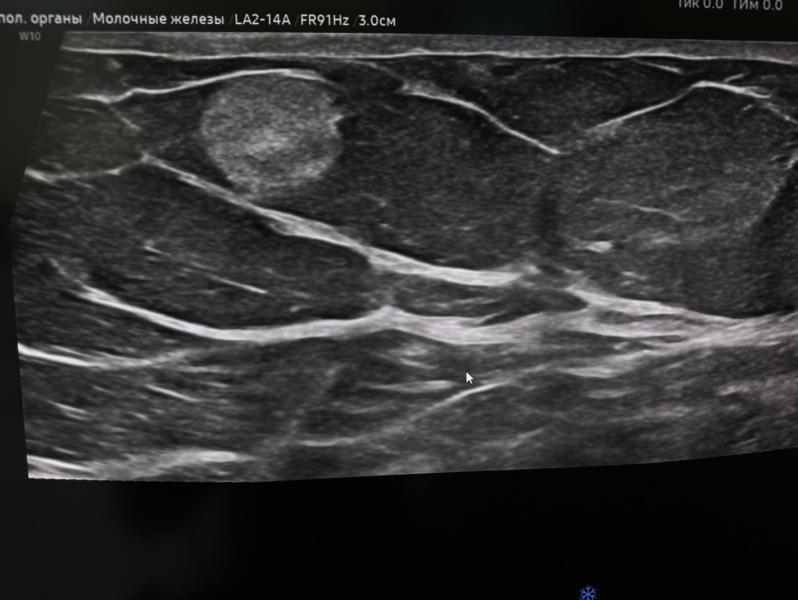

Липома молочной железы: удалять или наблюдать?

Липома молочной железы - это доброкачественное образование, не требующего хирургического вмешательства.

Наблюдение !

Хирургическое лечение показана в случае быстрого роста или же если вызывает дискомфорт у больного !